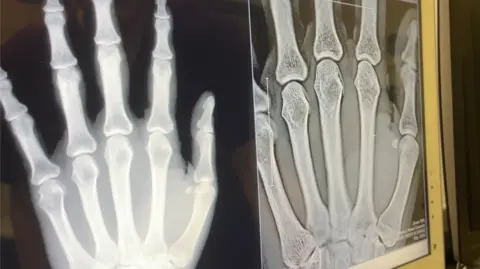

It is the first live trial of the portable imaging technology, which offers 3D imaging at a similar cost and radiation dose to traditional 2D X-rays, according to Karen Knapp, professor of musculoskeletal imaging at the University of Exeter.

Ms Knapp said the new technology, called AdaptixOrtho350, could help avoid permanent damage to joints by detecting diseases like rheumatoid arthritis at the earliest stages.

It works by creating 3D images from a stack of image slices, much like CT and MRI imaging, but with a lower radiation dose compared to CT, faster imaging, lower power requirements and a compact size, she added.

Ms Knapp said up to 50% of people with early joint changes due to rheumatoid arthritis were missed when diagnosed using 2D X-rays.

She said: “We’re really excited to be the first to trial the new Adaptix Ortho350, which promises much better visualisation of bone and joints than traditional 2D images.